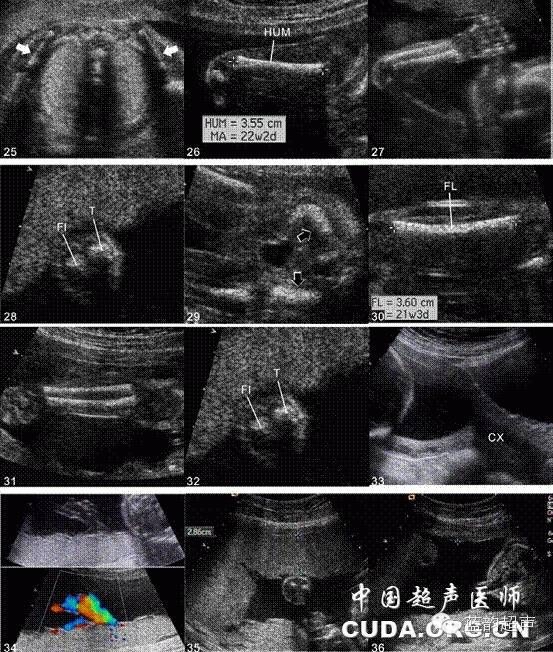

Ⅲ级产科超声检查建议存留的超声图与模式图

1、丘脑水平横切面超声图与模式图,2、侧脑室水平横切面超声图与模式图,3、小脑水平横切面超声图与模式图,4、鼻唇冠状切面超声图与模式图,5、双眼球水平横切面超声图与模式图,6、颜面部正中矢状切面超声图与模式图,7、四腔心切面超声图与模式图,8、左室流出道切面超声图与模式图,9、右室流出道切面超声图与模式图,10、三血管切面超声图与模式图,11、三血管气管切面超声图与模式图,12、测量胎心率图(多普勒或M型)超声图及模式图13、膈肌冠状切面超声图与模式图,14、右侧膈肌矢状切面超声图与模式图,15、左侧膈肌矢状切面超声图与模式图,16、上腹部横切面超声图与模式图,17、脐带腹壁入口腹部横切面超声图与模式图,18、脐动脉水平膀胱横切面超声图与模式图,19、双肾横切面超声图与模式图,20、左肾及右肾矢状切面超声图与模式图,21、双肾冠状切面超声图及模式图,22、脊柱矢状切面超声图及模式图,23、脊柱横切面超声图及模式图,24、脊柱冠状切面超声图及模式图25、肩胛骨水平横切面超声图及模式图,26、肱骨长轴切面超声图及模式图,27、尺桡骨长轴切面,28、尺桡骨短轴切面超声图及模式图,29、骼骨水平横切面超声图及模式图,30、股骨长轴切面超声图及模式图,31、胫腓骨长轴切面超声图及模式图,32、胫腓骨短轴切面超声图及模式图,33、孕妇宫颈内口矢状切面超声图及模式图,34、脐带胎盘入口切面超声图及模式图,35、胎盘厚度测量超声图及模式图,6、最大羊水池切面超声图及模式图